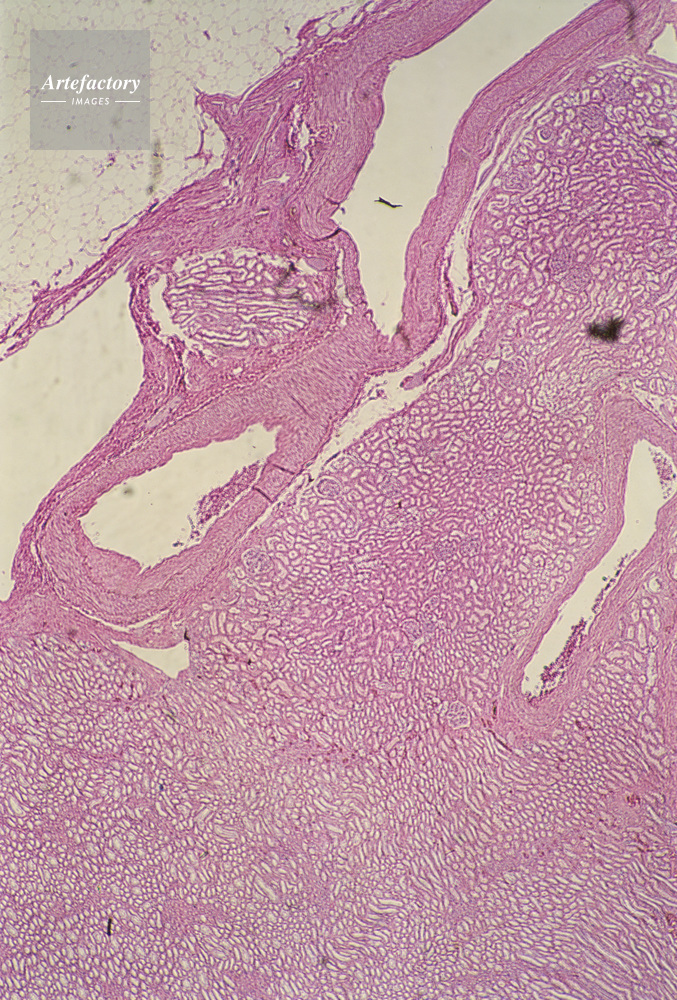

| キャプション | 腎臓円柱,人間,40倍 | 制限事項 | ||